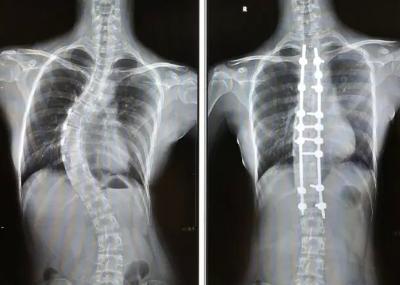

脊柱侧弯是一种常见的脊柱畸形 ,严重影响患者的生活质量。当保守治疗无效时,脊柱融合手术成为许多患者的最后选择。然而,这种手术虽然能够显著改善脊柱畸形,但也伴随着一些潜在的后遗症。

脊柱侧弯手术最常见的后遗症之一是 脊柱活动度的丧失 。由于手术需要植入内固定装置来矫正脊柱,这不可避免地会影响椎体之间的活动。一位接受过手术的患者曾表示:“手术后我感觉背部变得僵硬,有些动作做起来不如以前灵活了。”医生在手术前需要仔细评估,尽量保留患者一定的活动度,但这种权衡往往很困难。